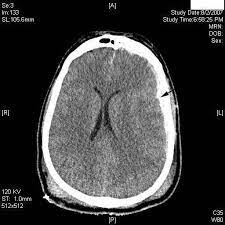

Pdf Hubungan Cedera Servikal Dengan Fraktur Depresi Tulang Frontal Pada Cedera Kepala Ringan Muhammad Arifin Academia Edu

Pdf Hubungan Cedera Servikal Dengan Fraktur Depresi Tulang Frontal Pada Cedera Kepala Ringan Muhammad Arifin Academia Edu from 0.academia-photos.com